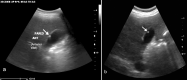

Methods: The teleultrasound system utilized in this study employs volume sweep imaging and a telemedicine app installed on a tablet which connects to an ultrasound machine. Volume sweep imaging is an ultrasound technique in which an individual scans the target region utilizing preset ultrasound sweeps demarcated by easily recognized external body landmarks. The sweeps are saved as video clips for later interpretation by an experienced radiologist. Teleultrasound scans from a Peruvian clinic obtained by individuals without prior ultrasound experience were sent to the United States for remote interpretation and quality assessment. Standard of care comparison was made to a same-day ultrasound examination performed by a radiologist.

Results: Individuals without prior ultrasound experience scanned 144 subjects. Image quality was rated "poor" on 36.8% of exams, "acceptable" on 38.9% of exams, and "excellent" on 24.3% of exams. Among telemedicine exams of "acceptable" or "excellent" image quality (n = 91), greater than 80% of the liver and gallbladder were visualized in the majority of cases. In this group, there was 95% agreement between standard of care and teleultrasound on whether an exam was normal or abnormal, with a Cohen's kappa of 0.84 (95% CI 0.7-0.98, p <0.0001). Finally, among these teleultrasound exams of "acceptable" or "excellent" image quality, the sensitivity for cholelithiasis was 93% (95% CI 68.1%-99.8%), and the specificity was 97% (95% CI 89.5%-99.6%).